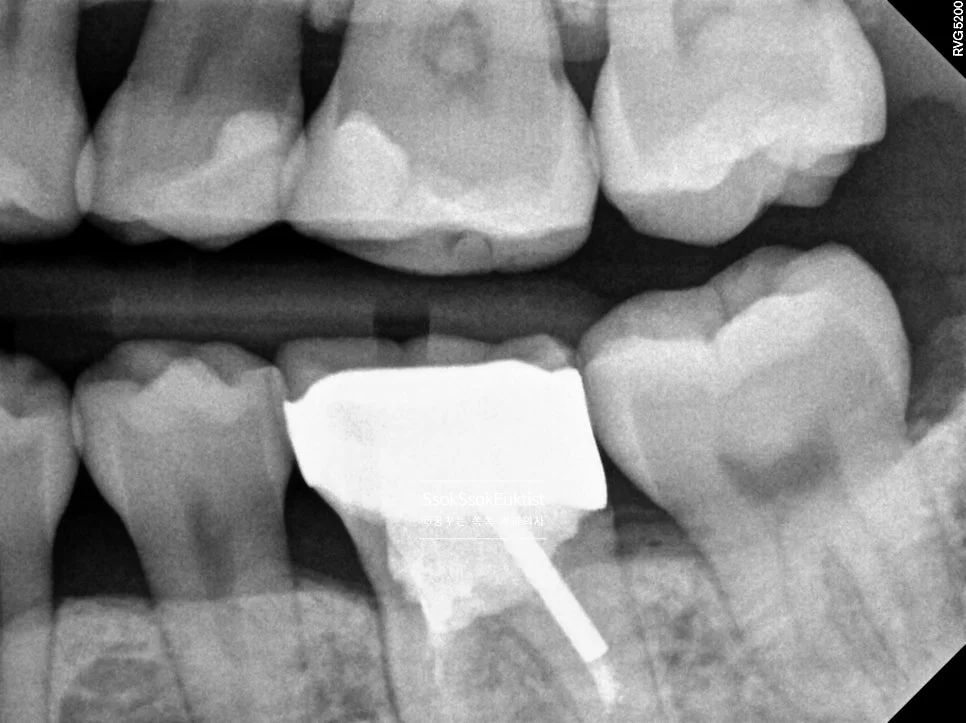

상악 교익 방사선 사진 충치 없음

상악 교익 방사선 — 충치 없음

하악 교익 방사선 사진 충치 없음

하악 교익 방사선 — 충치 없음

치아 사이 충치를 가장 잘 볼 수 있는 교익 방사선(Bitewing X-ray) 사진으로도 치료가 필요한 치아는 찾을 수 없었는데요.

왼쪽 위 앞니의 치경부 우식이 하나 있어 이것을 제외하고는 정말 스케일링만 진행하면 되는 상황입니다.